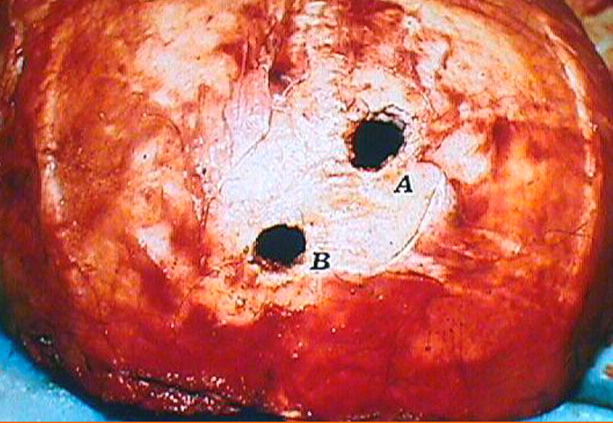

In figura si osservano due fori provocati da proiettili calibro 7,65 Browning a livello della teca cranica, osservati dal lato esterno (immagine superiore) e dal lato interna (immagine inferiore) di questa. È evidente l’erosione a spese del tavolato interno. Immagine tratta dal Libro “Patologia medico-legale e Tanatologia” di Vinci F. e altri autori.